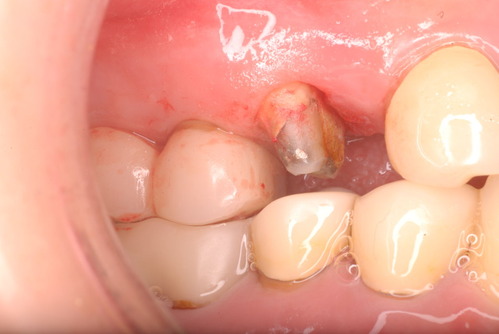

病気を治癒させずに矯正治療や破壊行為として神経を取り白い被せ物を入れた患者の末路です。

34才、奥歯や少し前の方の銀歯をセラミックなどの白いものに変更。

現在妊娠中で経過観察も中止。来院されたのはセラミックが取れたからでしたが、崩壊が激しく抜歯しかないような状態でした。それよりすべての歯は重症の歯周病に罹患していておそらく全ての歯は数年で抜け落ち、総義歯(総入れ歯)しかないと判断されたかたです。(そうはさせたくないのですが、本人は自覚していません。)

写真は殆ど崩壊し抜けたセラミックとその後修復してまだ経過監査中の歯の状態です。奥の歯は、重症の歯周病で注射もせずに抜いた歯です。